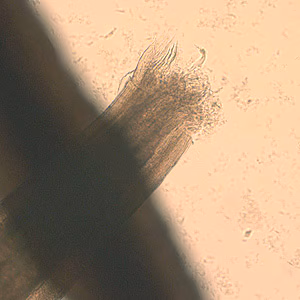

A 4-year-old boy’s parents discovered a worm that they thought had been spit out by their child. They submitted the worm to their physician, along with the information that the boy had some exposure to raw seafood and that the family had a dog. The worm was eventually sent to a state public health laboratory and then CDC for identification. The worm was approximately 2 cm in length (see Figure A). The worm was cleared with lacto-phenol but defining morphologic features could not be seen. The posterior end was difficult to examine due to the cuticle being “rolled up” (see Figure B, 40× magnification). The anterior end was broken off (see Figure C, 40× magnification). A small cross-sectional slice of the worm was obtained with a scalpel and placed on a microscope slide with the cut side facing up. A small amount of lacto-phenol was placed around the section and a coverslip “floated” gently onto it, with additional solution along the edges of the coverslip to make an effective seal. Figure D, taken at 100× magnification shows what was observed in the section. What is your diagnosis? Based on what criteria?

Figure B